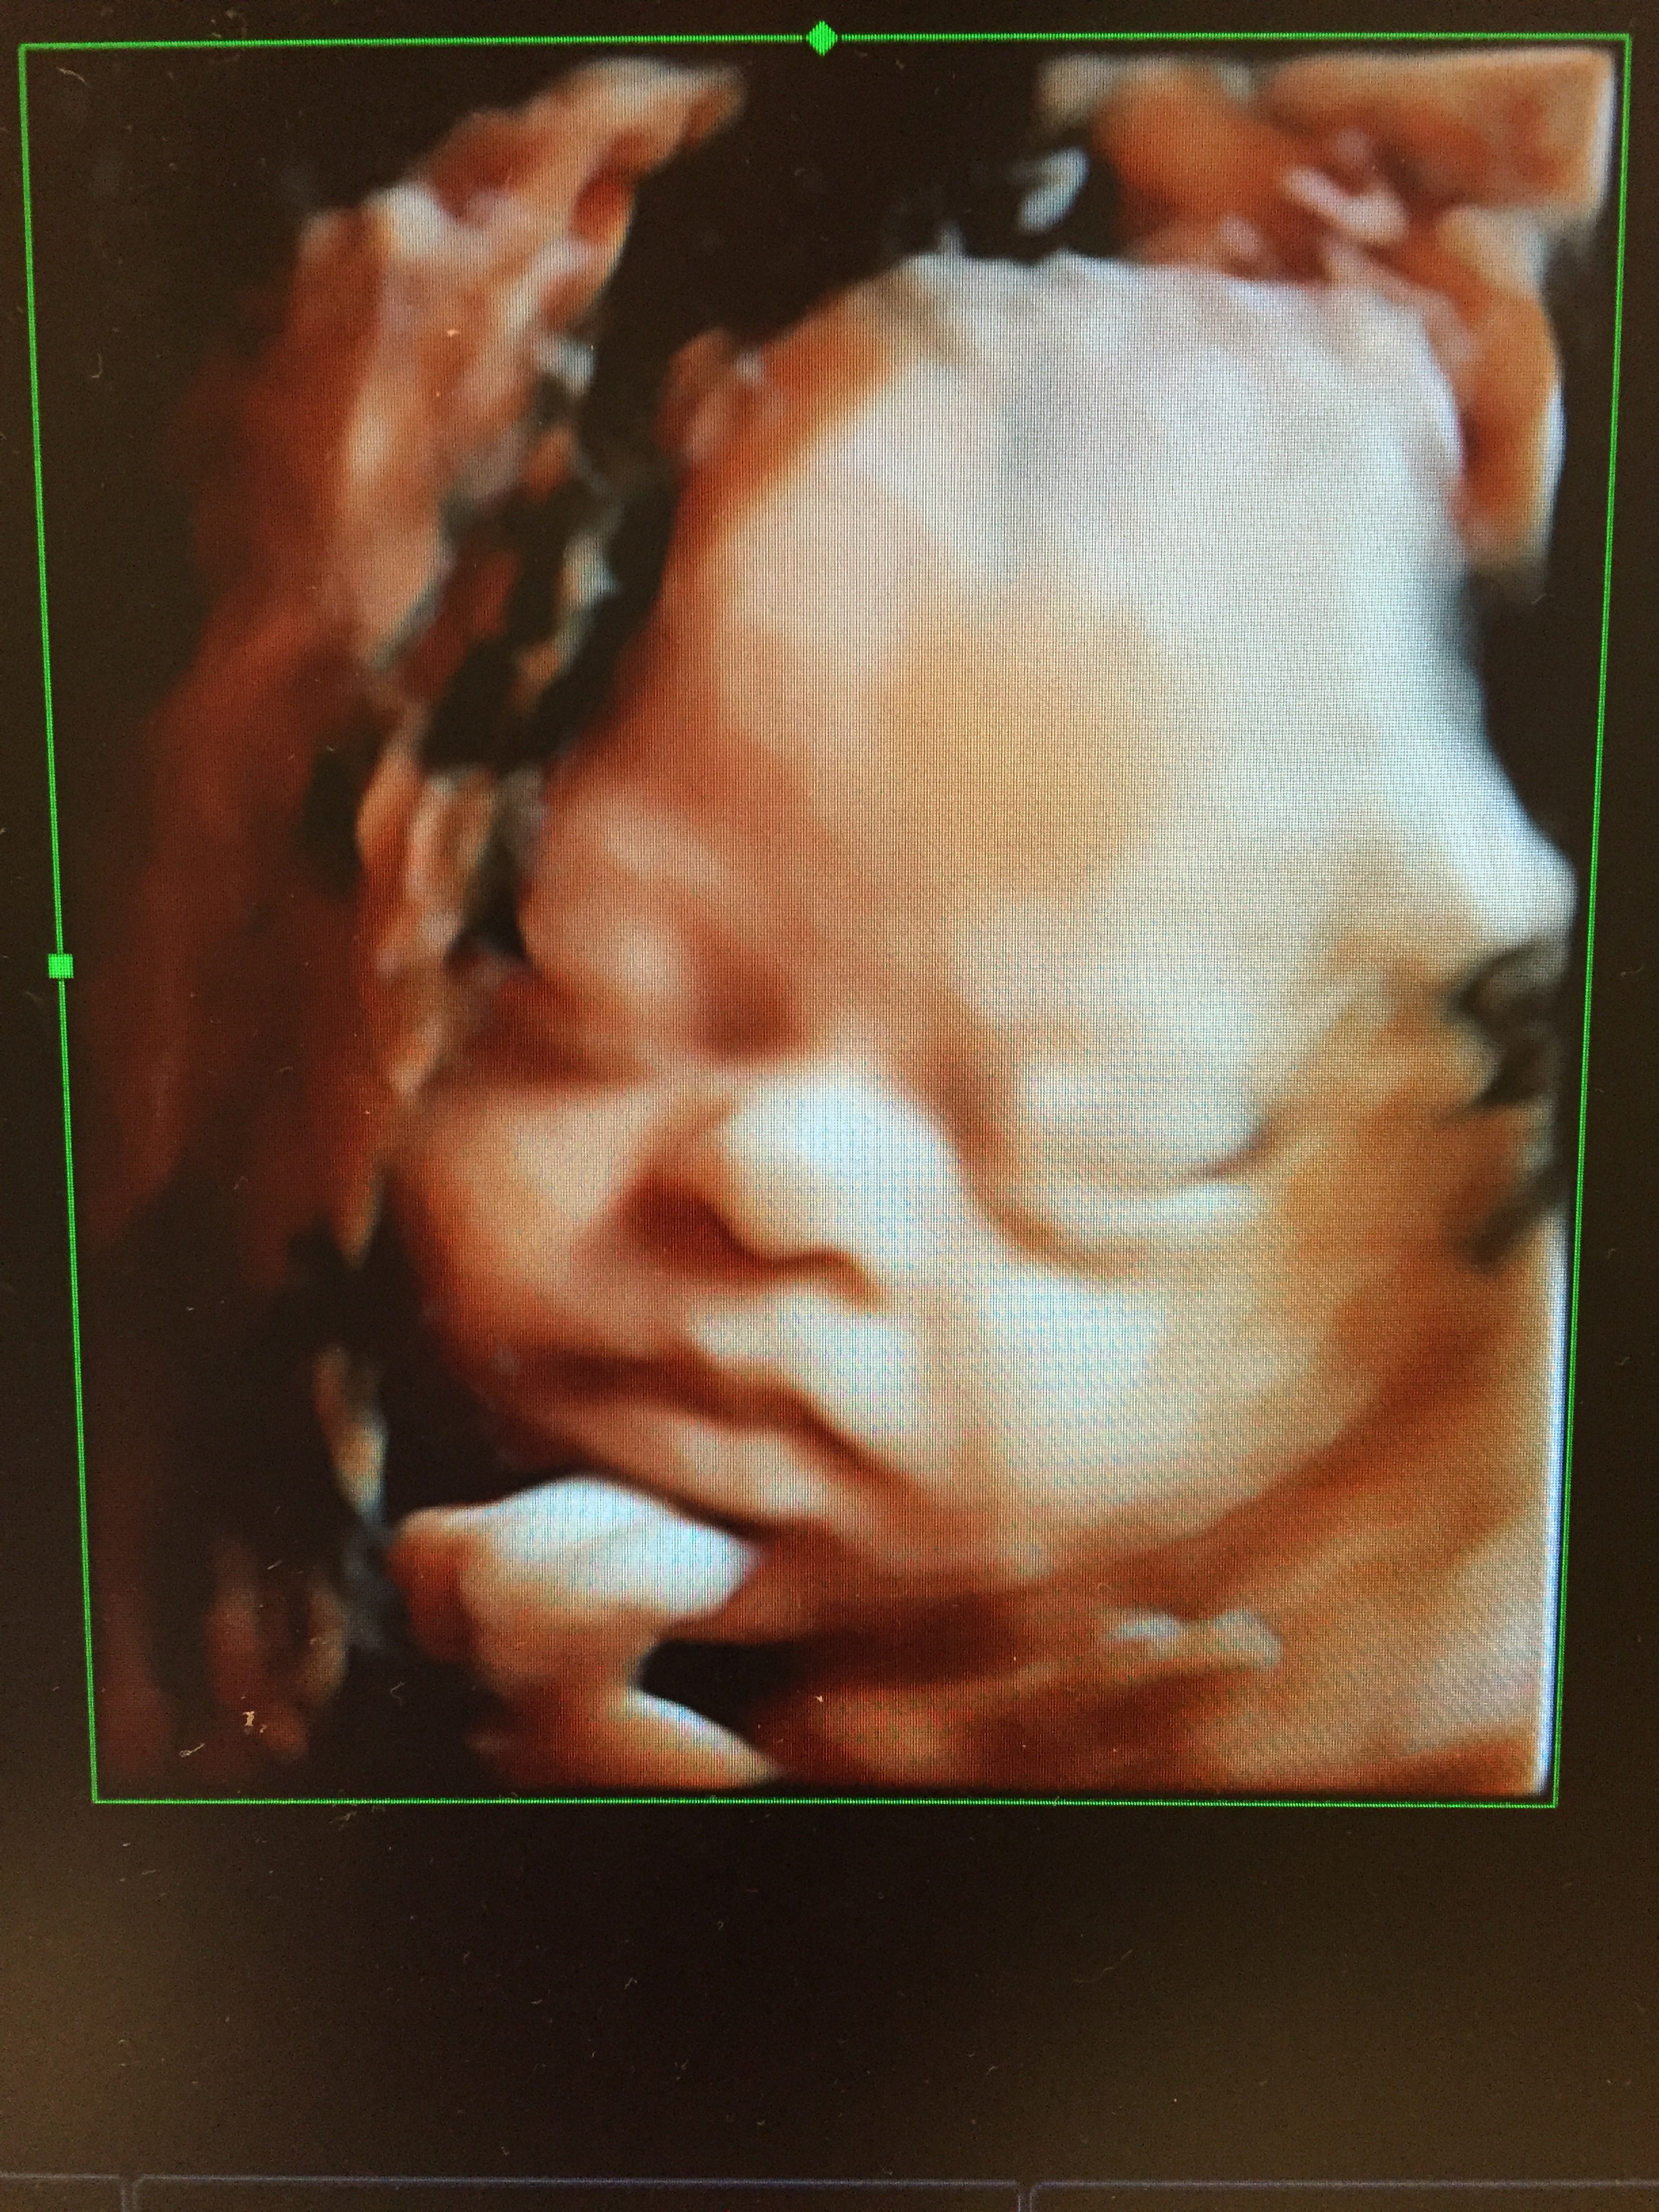

When I first learned that you were coming to be part of our family, I was so excited. I started to daydream about the little girl you would be. The games we would play, the fun we would have, the wonders you would discover.

But the more time I spent with you, holding you, playing with you, letting you fall asleep on my chest. And the more time I spent meeting other children with Down syndrome and talking to their parents, the less and less scared I became about the kind of person you would be and the kind of life you would live.

Because I started to see You and not just Down syndrome.

And you’re cute, and silly, and playful, and cranky, and stubborn, and kind and smart…And I’m confident that you will be able to do anything you set your mind to.